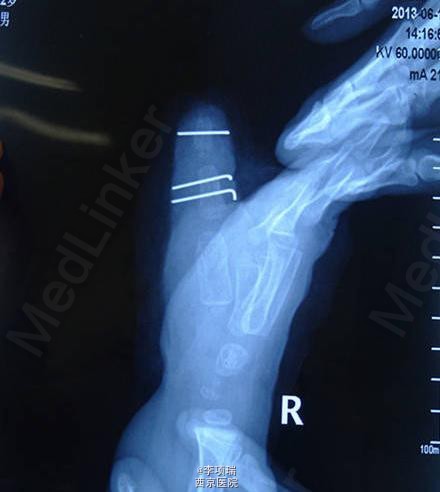

3型多指传统BC融合术

患儿,男,2岁4月,右拇3型复拇,家长选择融合术。